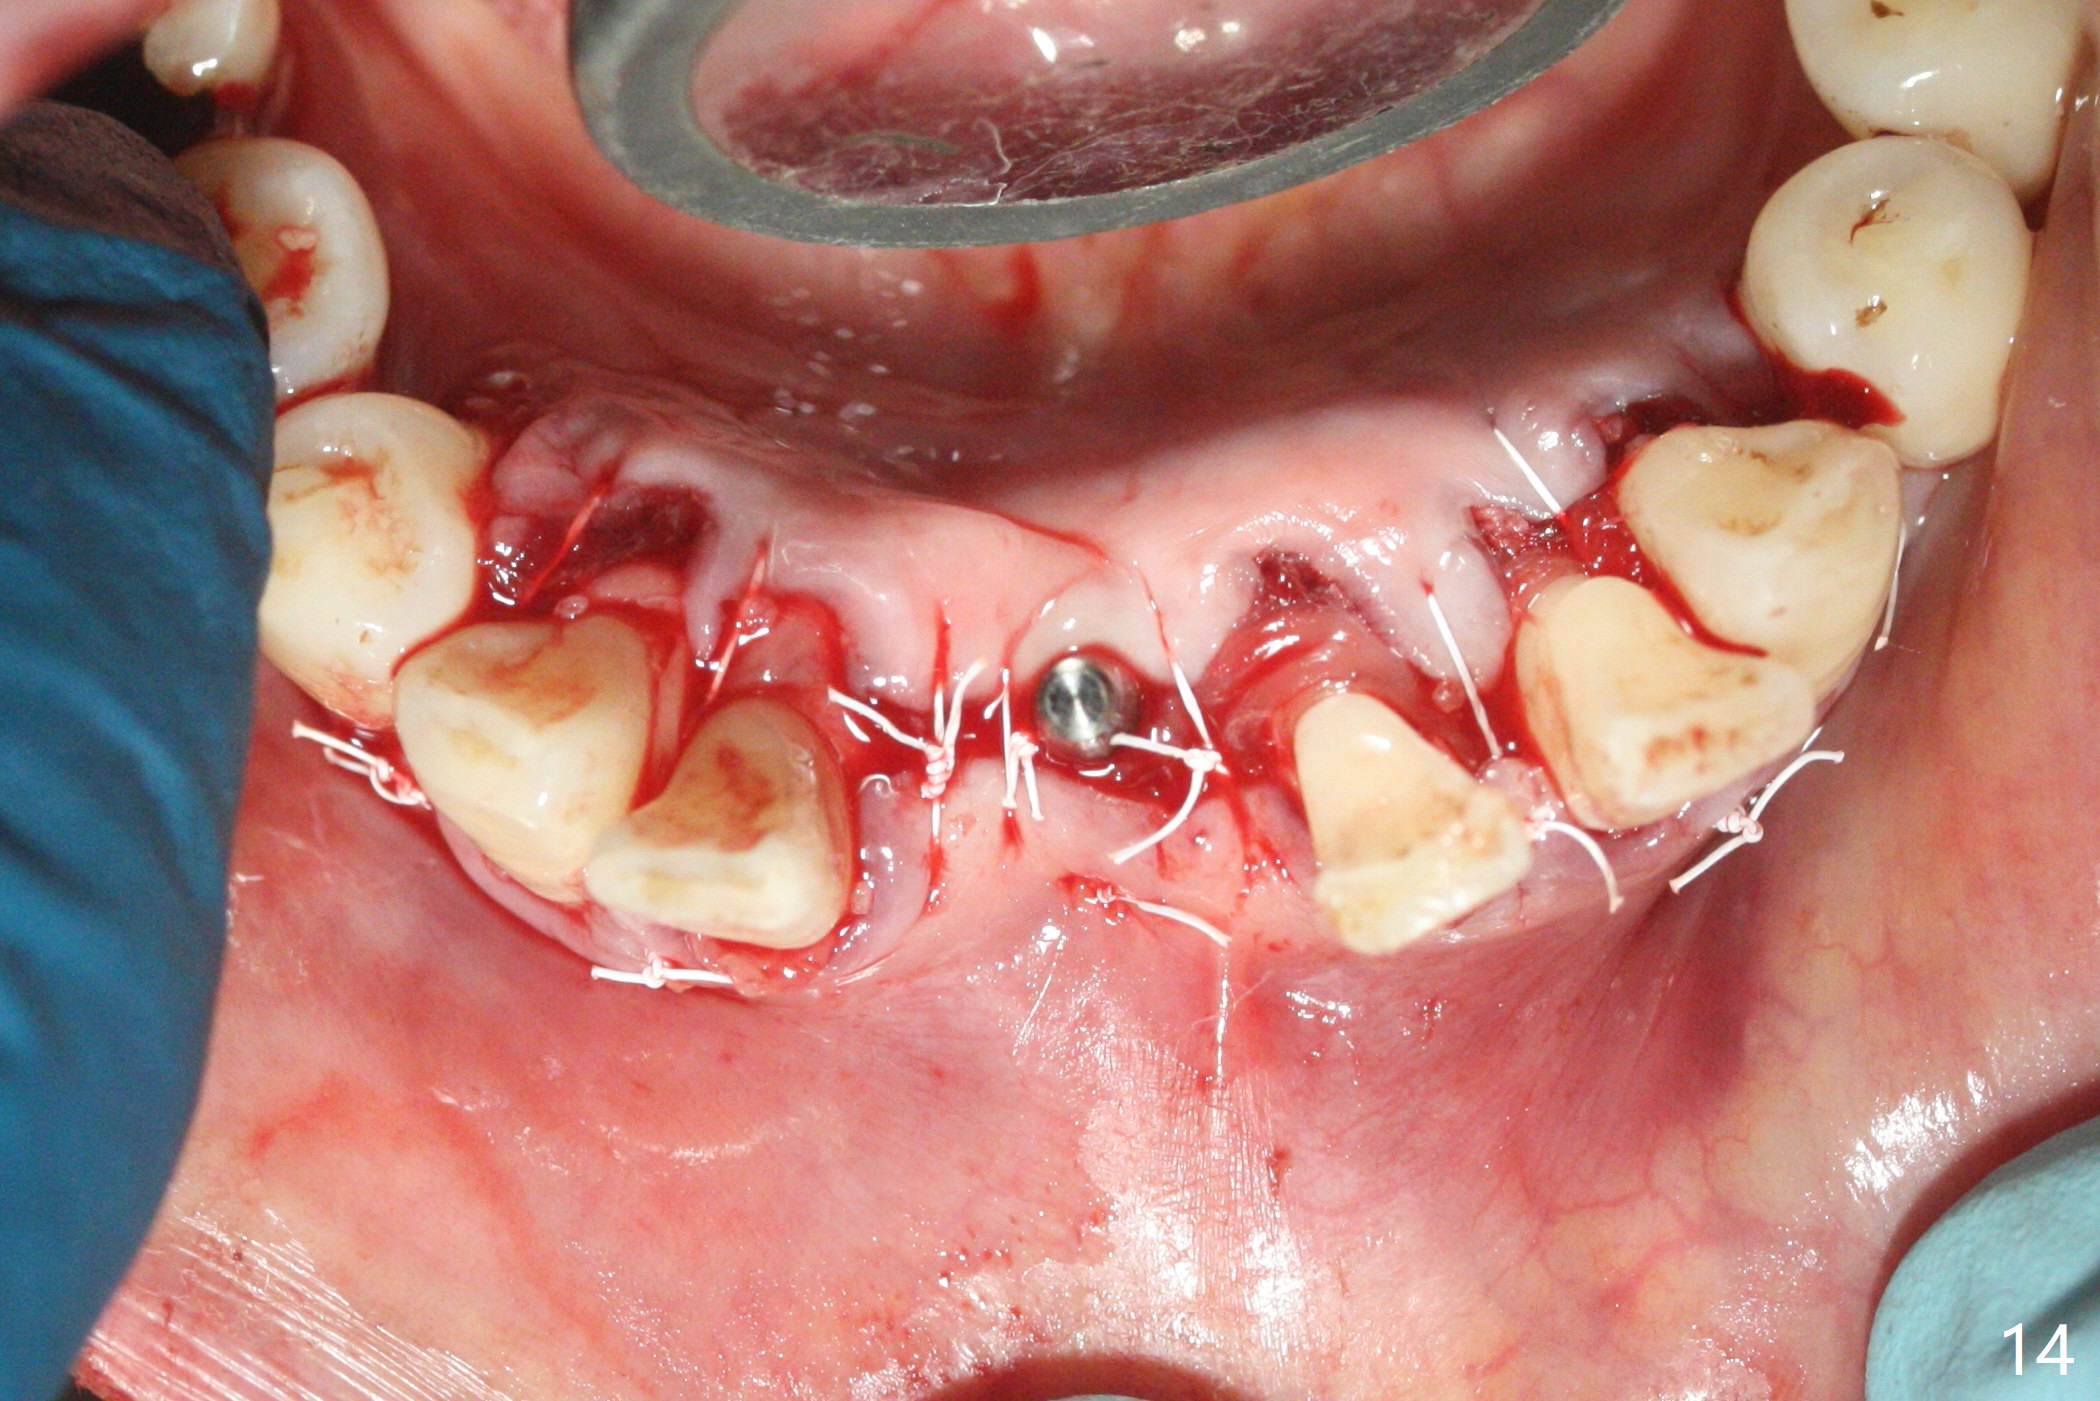

56岁女十分恐惧治疗,缺失右下1,其余切牙由于骨质吸收颊侧移位(图一:1,2),但是她不愿意拔除,同意右下1种植,牙周骨手术,植骨;植体整合后作为支抗,矫正移位下门牙。为了防止忘记舌侧瓣分离,先做舌侧切口(图二),然后颊侧瓣松弛分离(图三),包括使用前牙隧道刀(图四)切断颊侧骨膜,松弛到颊侧瓣能向舌侧牵拉3-4毫米(图五),舌侧瓣骨膜下广泛,深部分离(好像不能切断骨膜,图六),放置导板,磨平狭窄的牙槽嵴(图七:O(osteotomy)),植入2.5x12(4)毫米一段式植体(图八:故意舌侧植入,以便以后矫正),在颊侧骨板打多个出血洞(图八:箭头),然后把在平的器皿上形成的粘性骨板(sticky bone,图九),放置于植体和移位切牙周围(图十),接着使用消毒过的橡皮障punch(图十一(纸头相当于PRF膜;事先给助手示范))在三个PRF膜(图十二)打洞,套在植体和门牙上(图十三: 箭头),防止膜(图十四)和骨块(图十五,十六:*)移位,最后还必须使用最原始方法牙周敷料保护伤口(图十七)。术后9天,舌侧牙周敷料脱落,伤口稍微裂开(图十八)。术后18天撤除敷料,伤口裂开处有新鲜肉芽组织生长(图十九(*:下面是填入的骨粉,将是增宽的牙槽嵴(如果你是乐观主义者)),二十)。病人十分感激我们帮助她度过难关。她的确有sleep apnea,否定tongue thrust。术后三个月植体周围没有明显骨质吸收(图二十一至二十三),左下1,2轻度反合(图二十四),植体周围软组织健康(图二十五),5-5安置矫正器(图二十六,二十七,12 niti)。一周后下切牙向舌侧移动(图二十八),左下1,2反合纠正(图二十九)。再一周变化不大(图三十),植牙圈有些松动,两周后将重做临时牙冠,槽往舌侧移动。结果病人提前回来,植牙槽舌侧移位。一周后右下2不适(图三十一),尝试近中牵引(图三十二)。